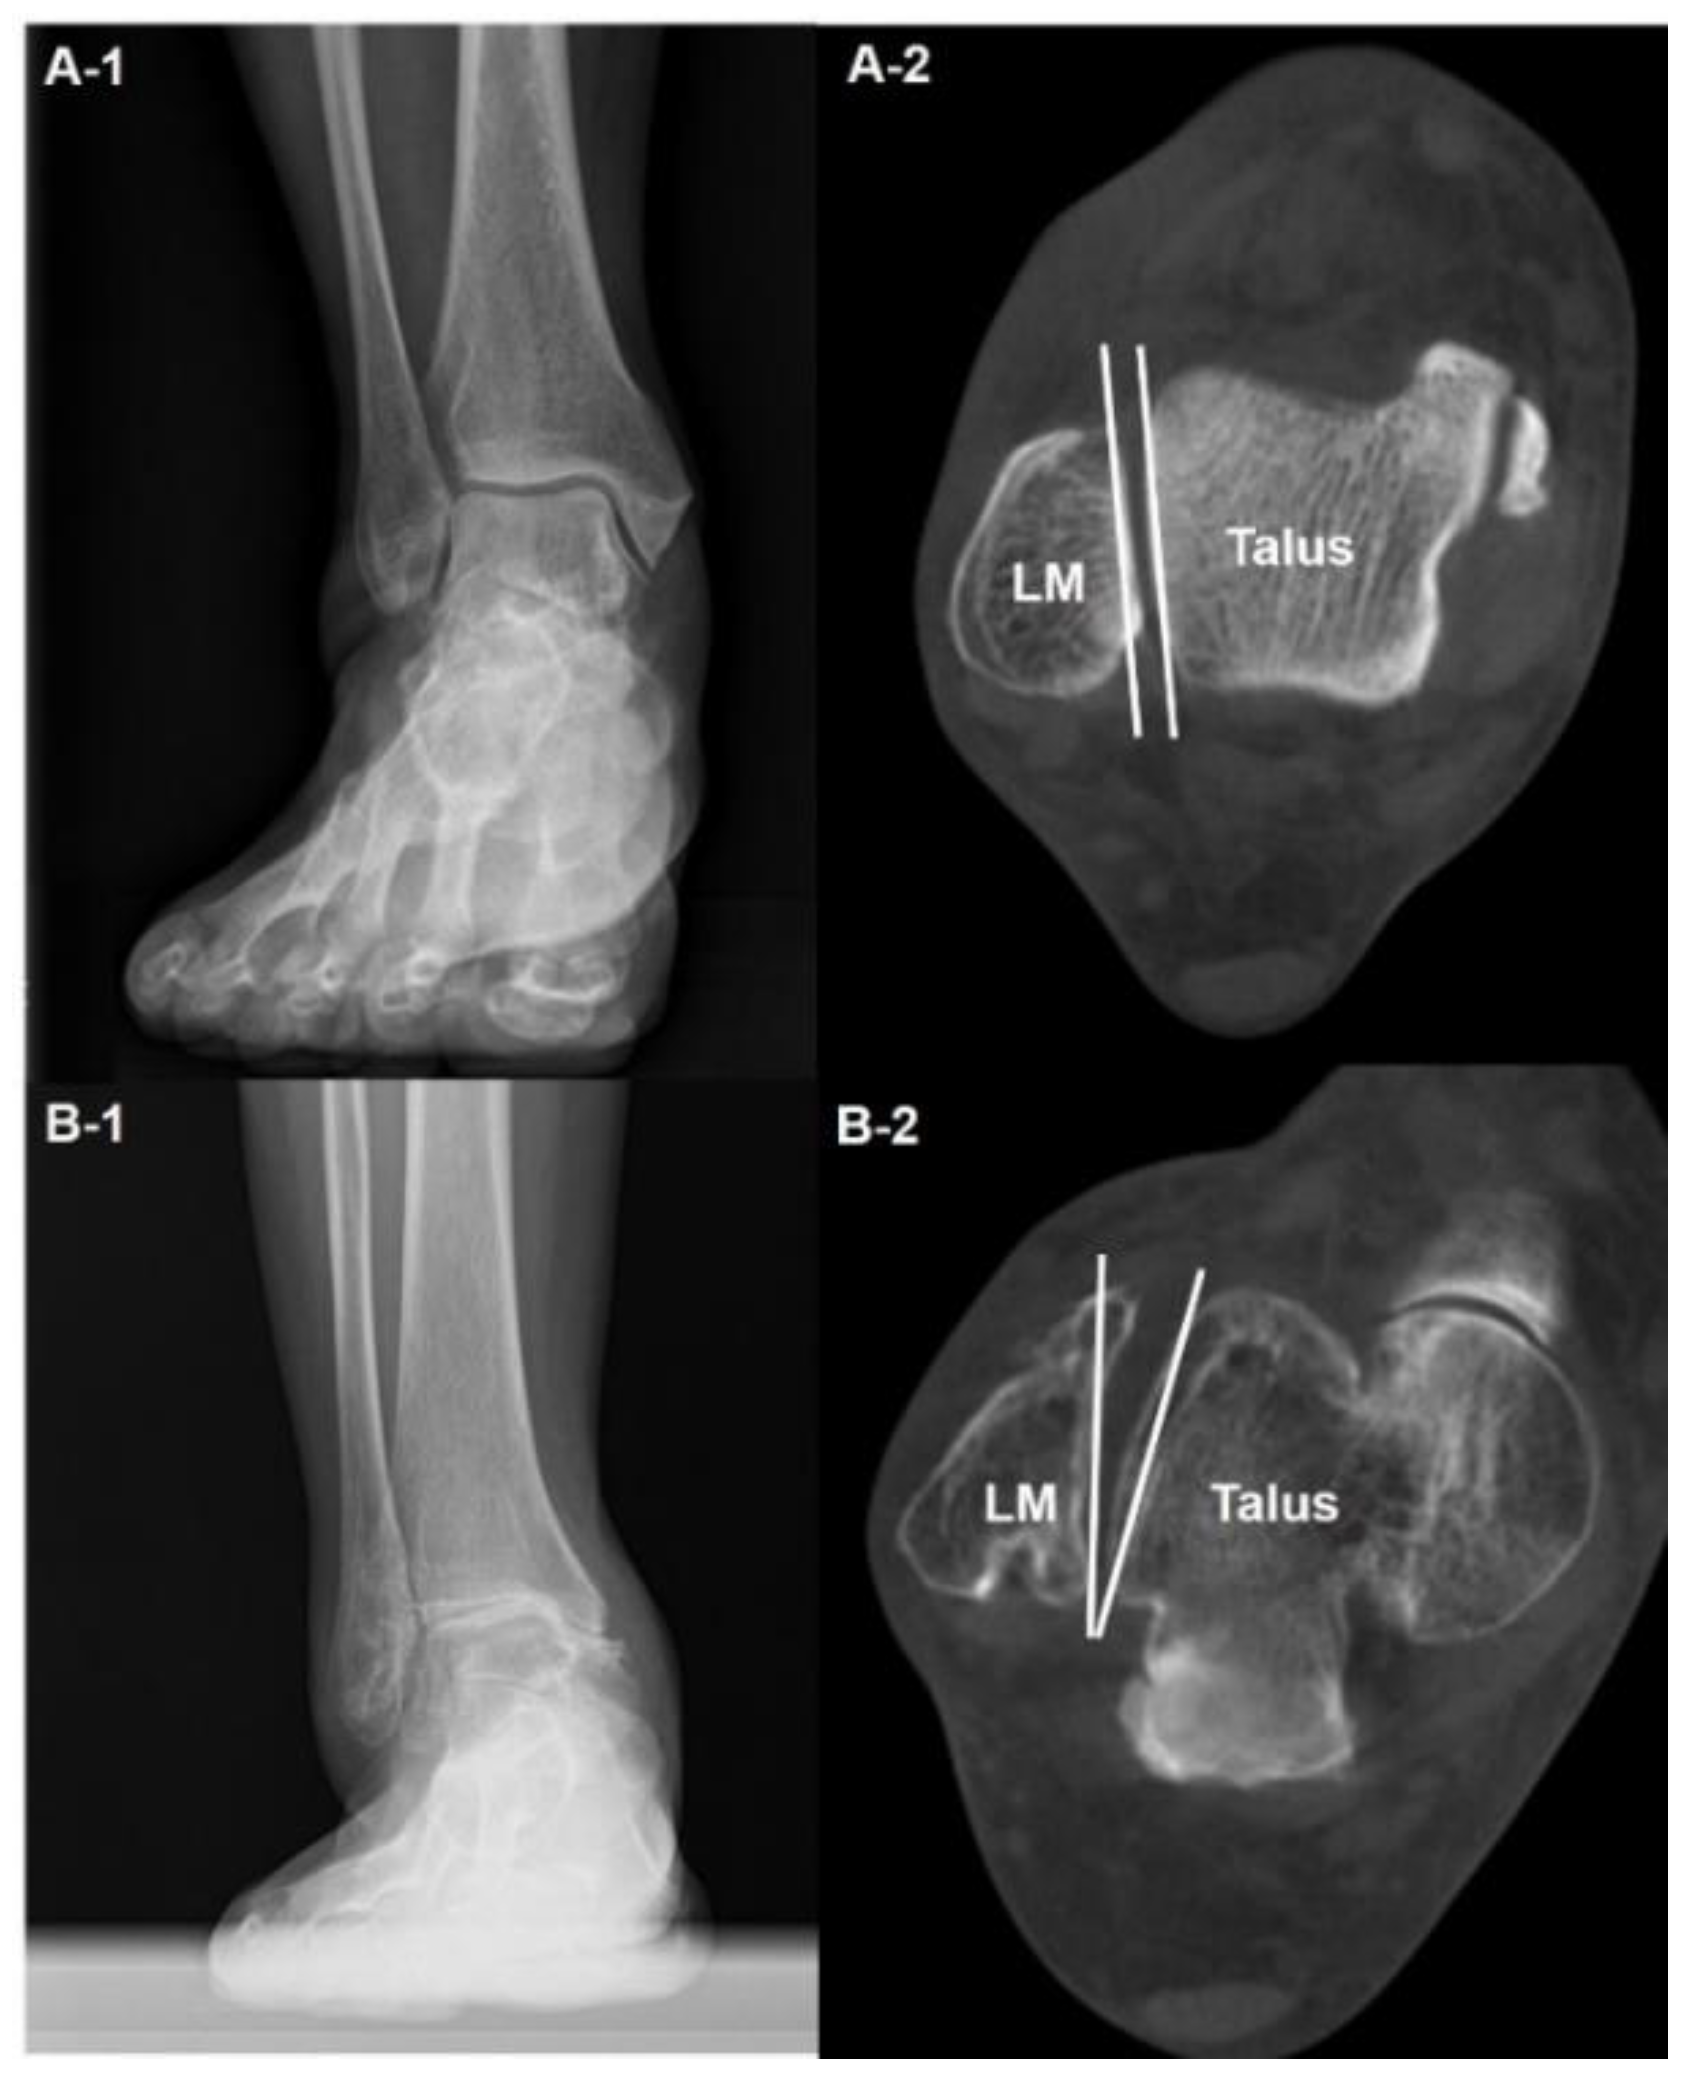

- Syndesmosis injury

- Kim, J.B.; Yi, Y.; Kim, J.Y.; Cho, J.H.; Kwon, M.S.; Choi, S.H.; Lee, W.C. Weight-bearing computed tomography findings in varus ankle osteoarthritis: abnormal internal rotation of the talus in the axial plane. Skeletal Radiol 2017, 46, 1071–1080. [Google Scholar] [CrossRef]